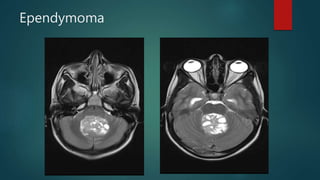

Ependymoma

• #31 Post contrast T1 axial imaging demonstrates bilateral enhancing masses in the cerebellopontine angle, larger on the left. Both can be seen extending into the internal acoustic meatii and are consistent with acoustic schwannomas. The fact that they are bilateral almost certainly indicates that the patient has NF2.  There are multiple enhancing nodular lesions spread throughout all the spinal canal and going through some vertebral foramina Mixed solid-cystic mass arising from the fourth ventricle and causing mass effect on the brainstem. There was also resultant obstructive hydrocephalus, not shown here. The mass appears to ‘ooze’ out of the foramen of Magendie. There was no associated spinal lesion. Classical ‘plastic’ ependymoma